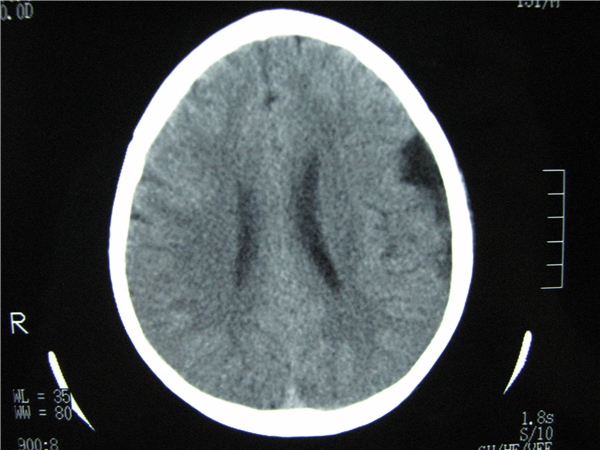

标题: CT20748:M 15Y 头痛,以前有外伤史请老师看看除了囊肿还有别 [打印本页]

标题: CT20748:M 15Y 头痛,以前有外伤史请老师看看除了囊肿还有别

m 15y 头痛,以前有外伤史请老师看看除了囊肿还有别的吗?

双侧侧裂池和纵裂池近前颅窝蛛网膜囊肿。

额叶哪要是容积效应,或不是脂肪就没看见别的了

无明显占位及负占位效应,考虑软化灶并脑室穿通畸形囊肿、局限性脑萎缩